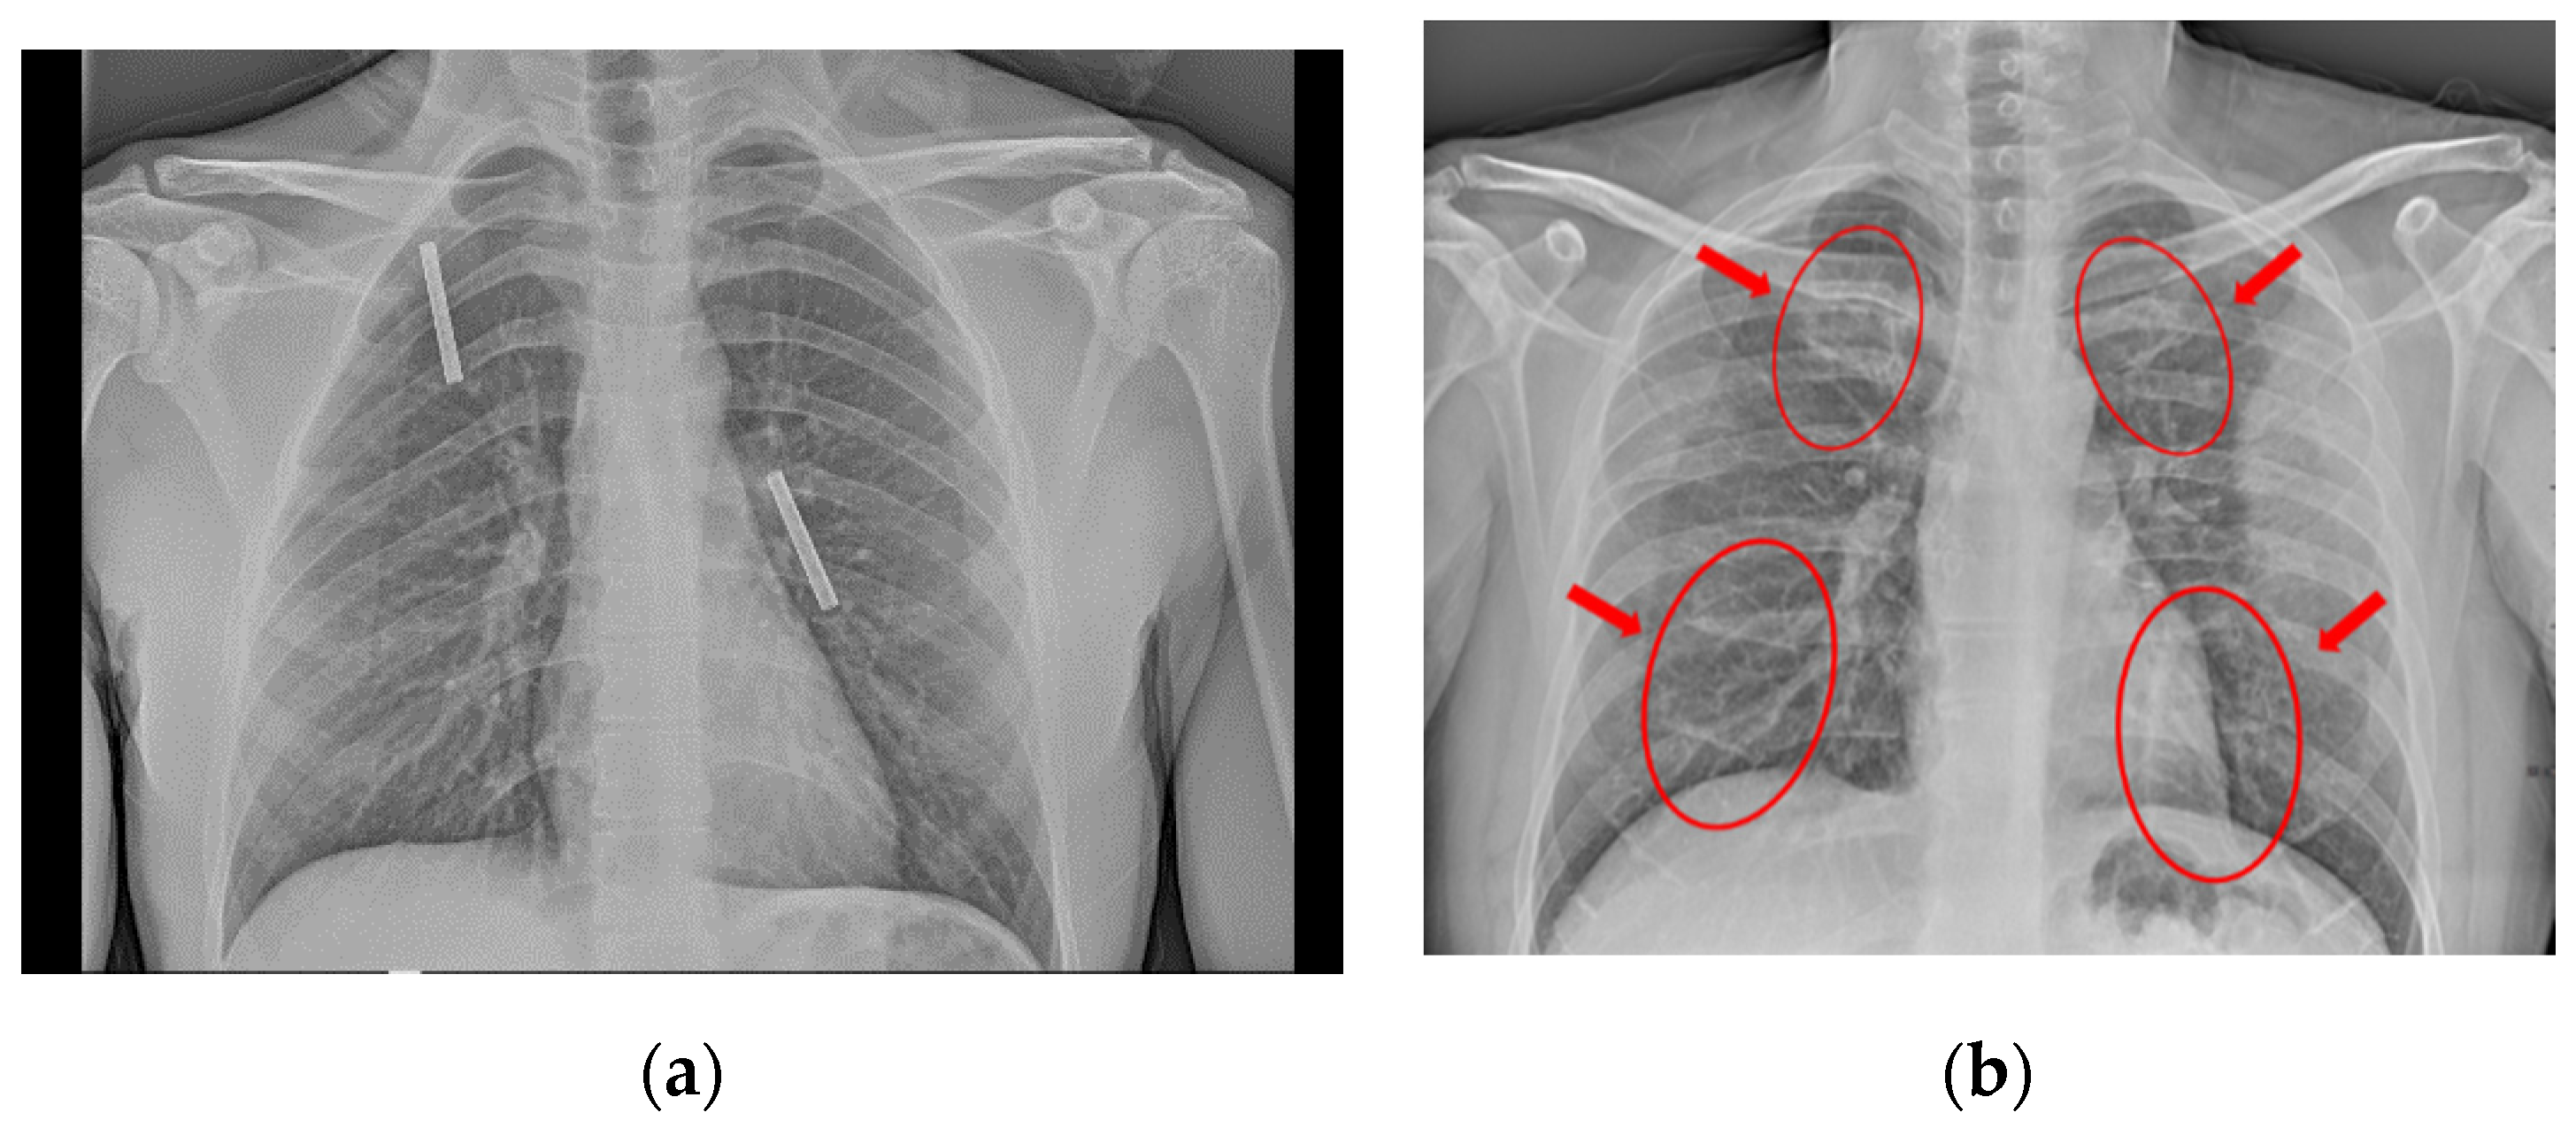

3.1. Pneumonia Dataset

3.2. COVID-19 Dataset